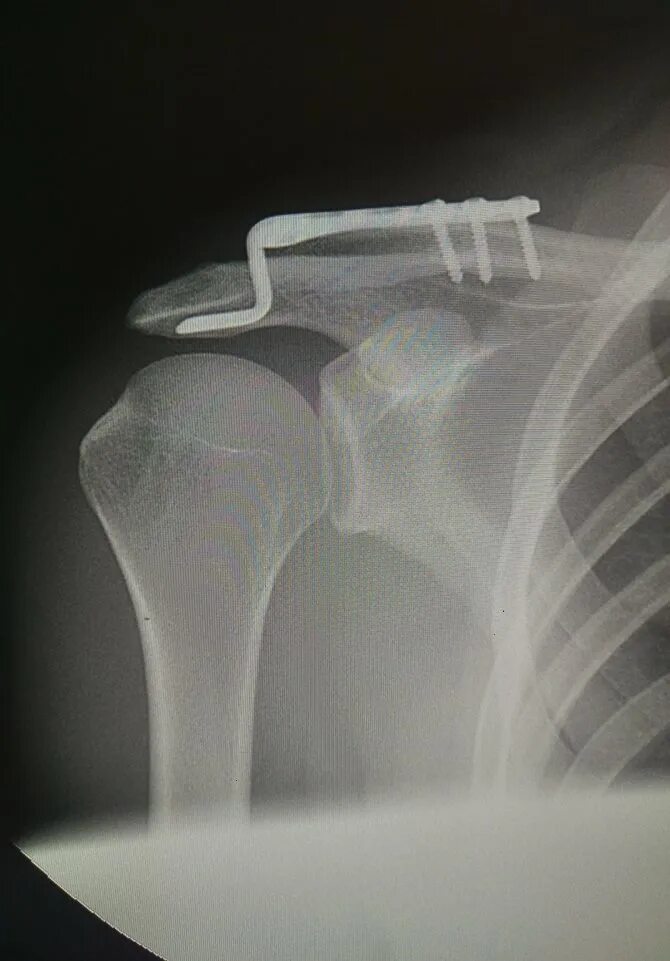

Деформирующий акромиально ключичного сочленения